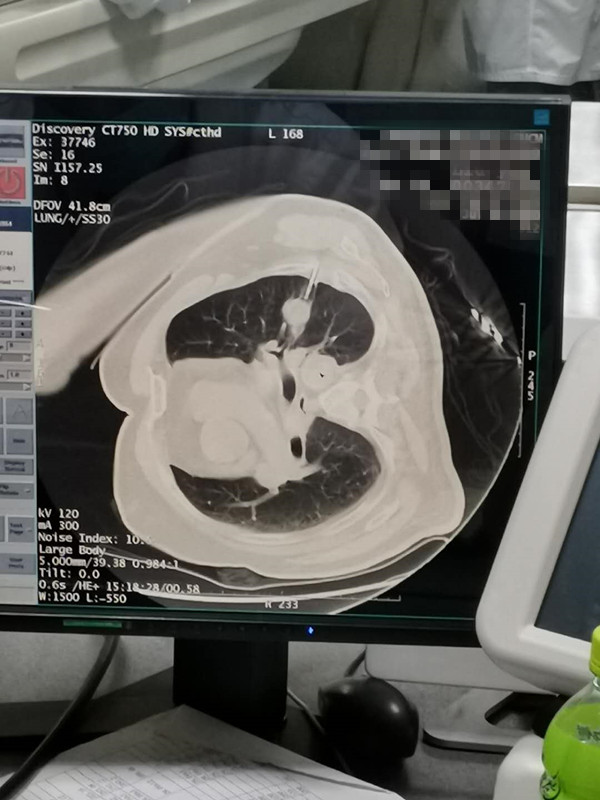

75岁肺部氩氦刀冷冻消融

发布人:美国氩氦刀技术官方网站    发布时间:2020/7/31 14:32:13